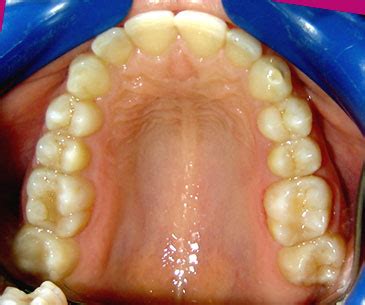

Una vez finalizado el tratamiento conseguimos los objetivos marcados:

- Espacios de extracciones perfectamente cerrados. Sin riesgo de que vuelvan a abrirse con el tiempo.

- Corrección de la protrusión de los dientes superiores. Incisivos superiores en posición correcta y no salidos o adelantados.

- Alineamiento correcto de los dientes superiores.

- Corrección de la línea media y mejora de la sonrisa.